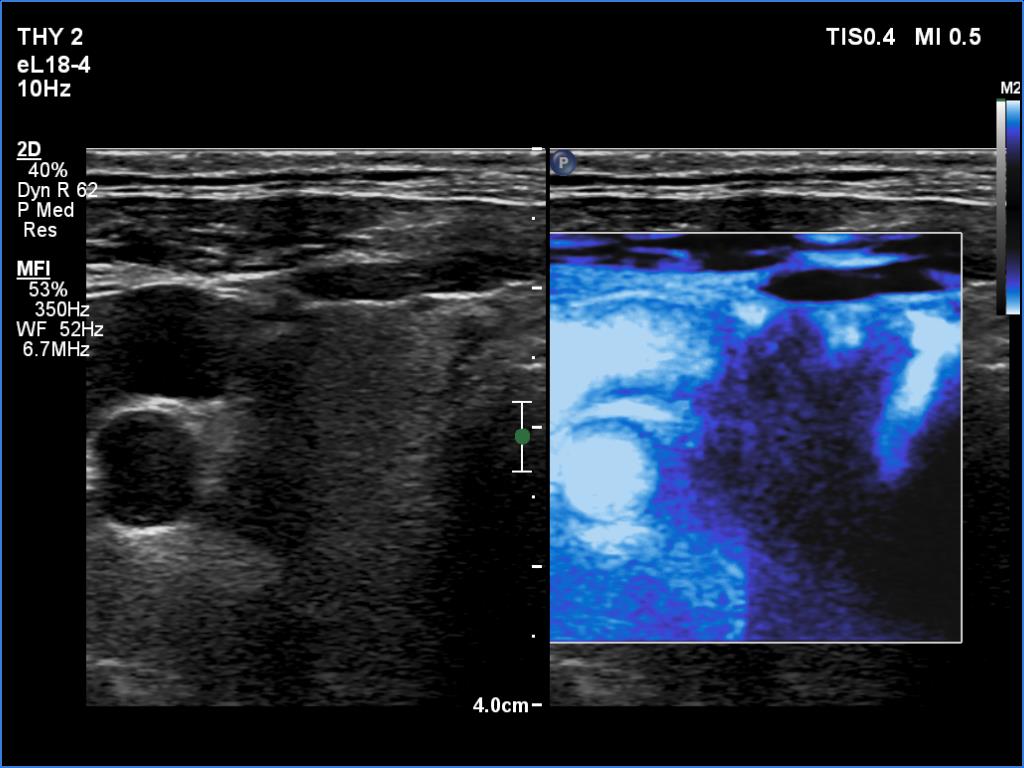

Ultrasonography. The right lobe was echonormal and intact. A large mass occupied almost the entire left lobe. On this side, normal thyroid tissue could only be identified in the dorsal part. The mass was composed of echonormal and hypoechoic areas, had macrocalcifications, irregular intranodular vascularity and proved to be very hard on elastography. There were multiple lymph nodes in III, IV and V left neck compartments. One of the nodes was in close proximity to the jugular vein and was suspicious of having broken into the vessel. The trachea was significantly narrowed at the lower level of the thyroid.

2. There are several remarkable findings in this case, e.g., the destruction of the left lobe by the tumor, the elastography pattern, the relation of the largest metastatic lymph node and the jugular vein, the ultrasound demonstration of the trachea' stricture.